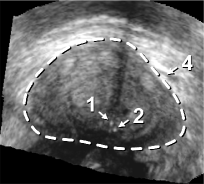

The framework was validated on 278 registrations of 295 US volumes from 17 patients. The 17 reference images were acquired shortly before the intervention, and the tracking images were acquired after a biopsy shot. The clinical protocol was approved by the ethical committee of the XXX hospital, Town, Country, and all patients consented to participate to the study. The images were acquired with a GE Voluson and a RIC5-9 endorectal US probe. The algorithms were executed on a 4-core 2.6Ghz processor. In order to provide a reference gold standard for the evaluation of registration accuracy, experts manually segmented 467 point fiducials that were clearly identifiable on multiple images (e.g. calcifications and cysts). The distances between fiducial pairs were measured after registration to estimate the local accuracy. Note that the unavoidable segmentation error increases the measured error in average; this approach hence underestimates accuracy. Accuracy was computed for all registrations that were qualified as valid by experts after visual inspection, which represent 97,8 of the registrations. The results for both rigid and elastic registration are given in Tab. 1, and a visual illustration of the registration performance is given in Fig. 2. Fig. 3 shows 3D biopsy maps created with our biopsy tracking system.